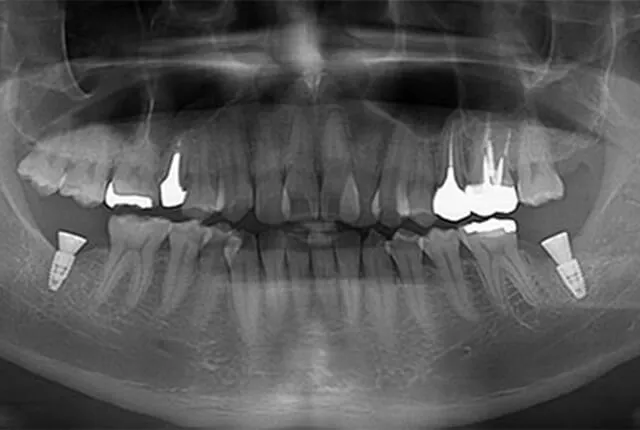

下の7番を抜歯して10年以上経過していますが、周囲の歯が動いた形跡がなく日常生活に何の支障もない方の例もあります。上の歯を欠損放置しても下の歯が伸びてこない場合もよくあります。

左下7番を抜歯した後、上の7番が伸びてこないタイプの歯であった

左下の欠損放置から数年、上の歯がほとんど動かなかったことはよかったことです。もし、左上7番が伸びて歯肉ギリギリまで出てきてしまっていたら、入れ歯もインプラントも入れることができませんでした。そこは幸運だったと思います。